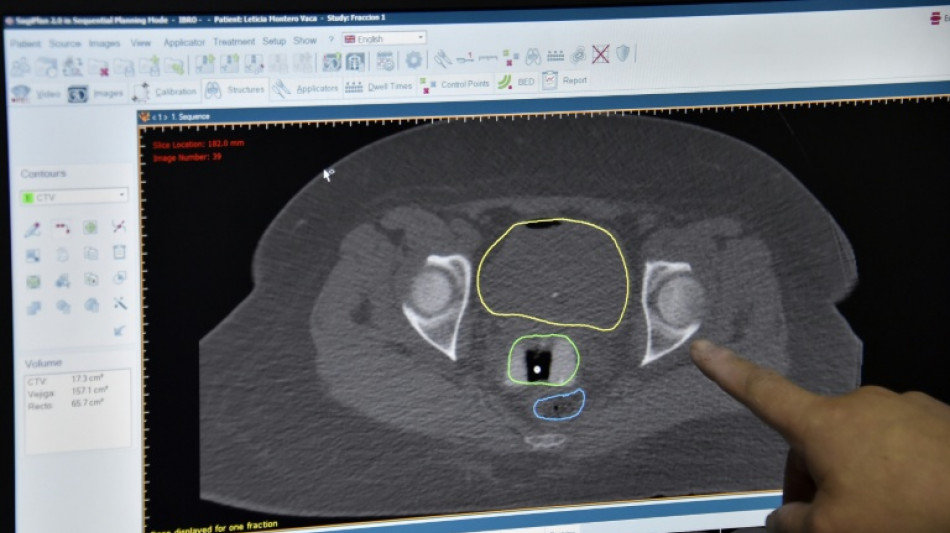

New cancer plan urged as survival improvements in England slow

Improvements in cancer survival rates in England and Wales have slowed down significantly since 2010, according to a major study released Wednesday, leading to calls for an urgent national cancer plan.

The study, conducted by the London School of Hygiene and Tropical Medicine, measured the survival index for 10.8 million adults diagnosed with cancer between 1971 and 2018, accounting for variables like age, sex, and cancer type.

It found substantial improvements over the 48-year period, with the five-year survival index increasing from 28.8 percent in 1971–72 to 56.6 percent in 2018.

However, the pace of progress has slowed in recent years.

The 10-year survival index improved by four percent between 2000–01 and 2005–06 and only 1.4 percent between 2010–11 and 2015–16.

The slowdown since 2010 "is likely to be at least partly explained by longer waits for diagnosis and treatment," said the report.

The deceleration has been observed across many individual cancers, "implying a system-wide challenge," said the study, funded by the Cancer Research UK charity.

Most notably, the 10-year survival index for breast, cervix, rectum, prostate, testis, and uterus cancers plateaued in the last 10–15 years, while the index for larynx cancers decreased.

Pancreatic cancer survival, at 4.3 percent in 2018, has shown minimal change since 1971–72.

The study calls for a "new, long-term National Cancer Plan" to "bring cancer survival trends back towards the best in the world".

National cancer strategies have been part of health policy in England and Wales since 2000.

The fourth national cancer strategy was published in 2015 but is now considered outdated as the current trajectory has failed to match its ambitious targets.

Plans for a fifth plan were withdrawn in January 2023, "leaving England as one of the few high-income countries in which a national cancer plan was not a central pillar of national health policy," said the report.